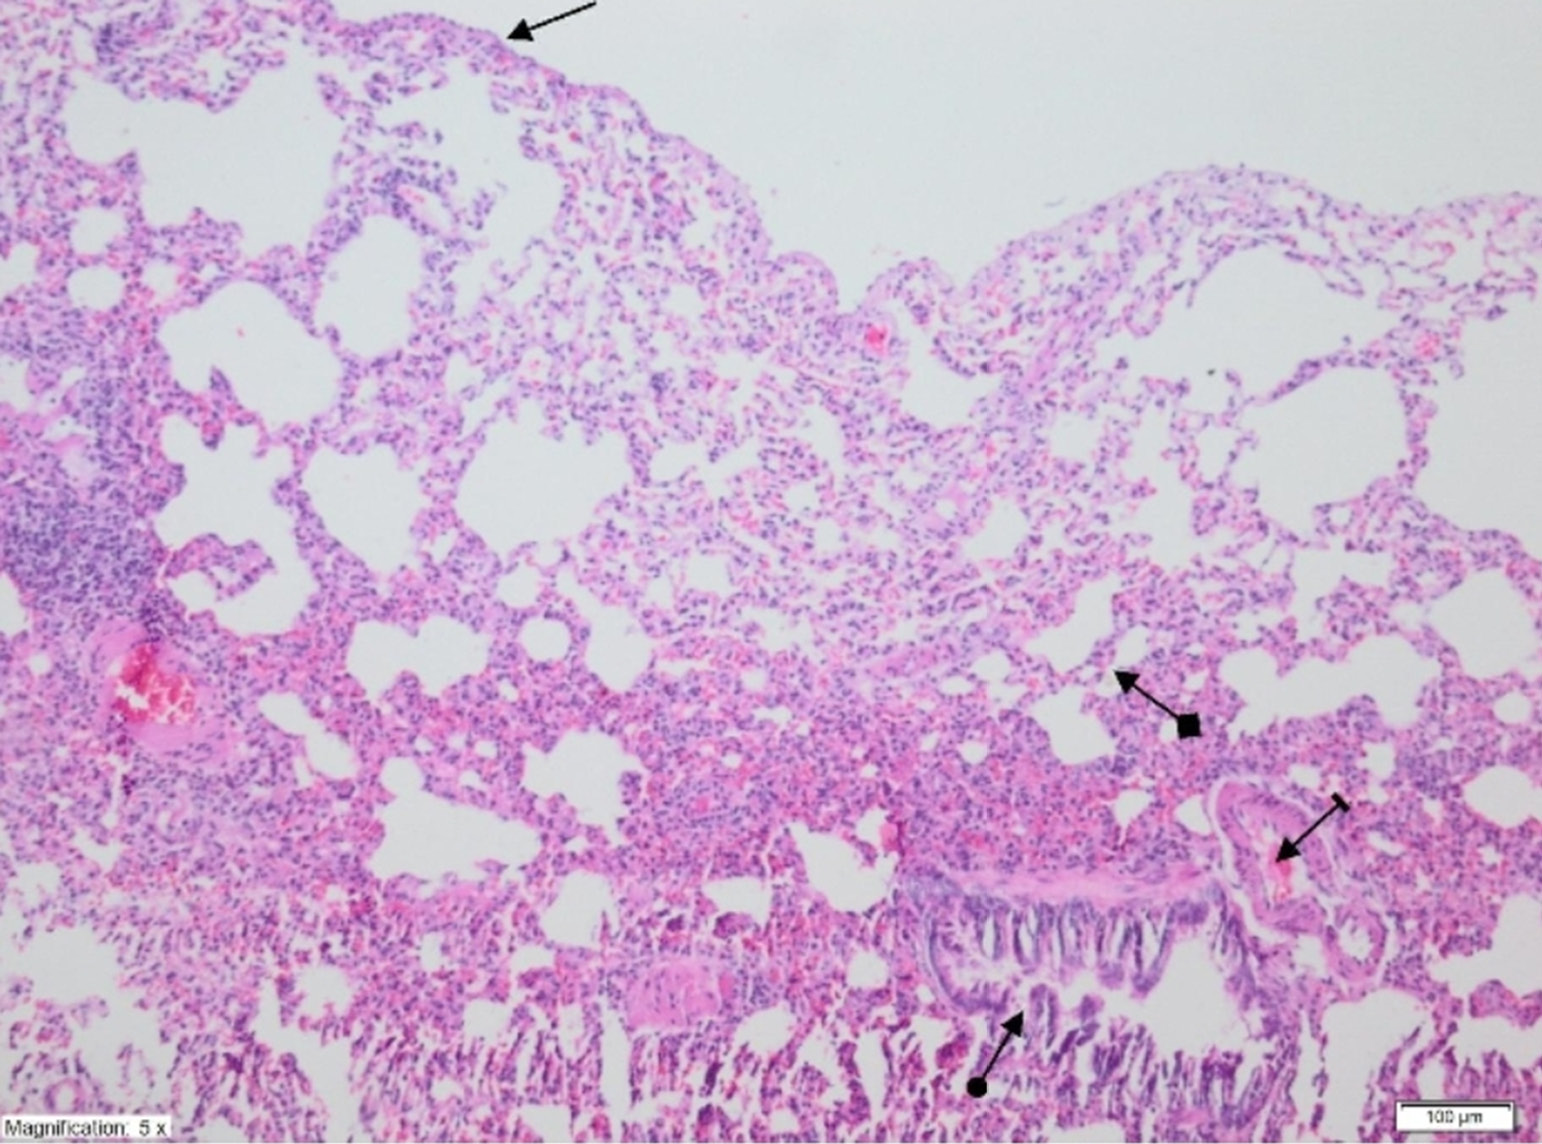

On histopathological examination, the alveolar vein, bronchiole structures and pleural mesothelium were identified as normal in pulmonary tissues in the SG group (Figure 4). However, significant areas of alveolar degeneration, edema and hemorrhage were observed in the pulmonary tissues of the LIR group (Figure 5). Congestion, PMNL and lymphocytic infiltration were observed in the lung tissues in the LIR group (Figure 6). In the lung tissue of the RLIR group, the pleural mesothelium, and alveolar, vascular and bronchial structures were identified as normal, which was similar to the observations in the SG group (Figure 7).